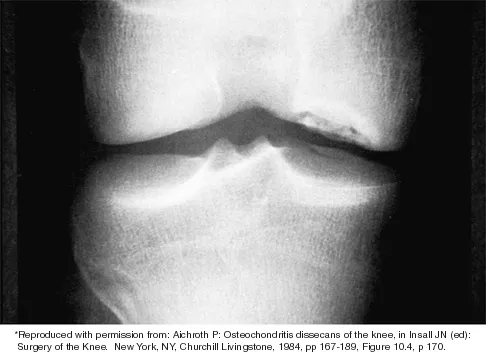

Question 34

Which of the following primary prognostic factors best predicts the outcome of the knee lesion shown in Figure 22?

Explanation